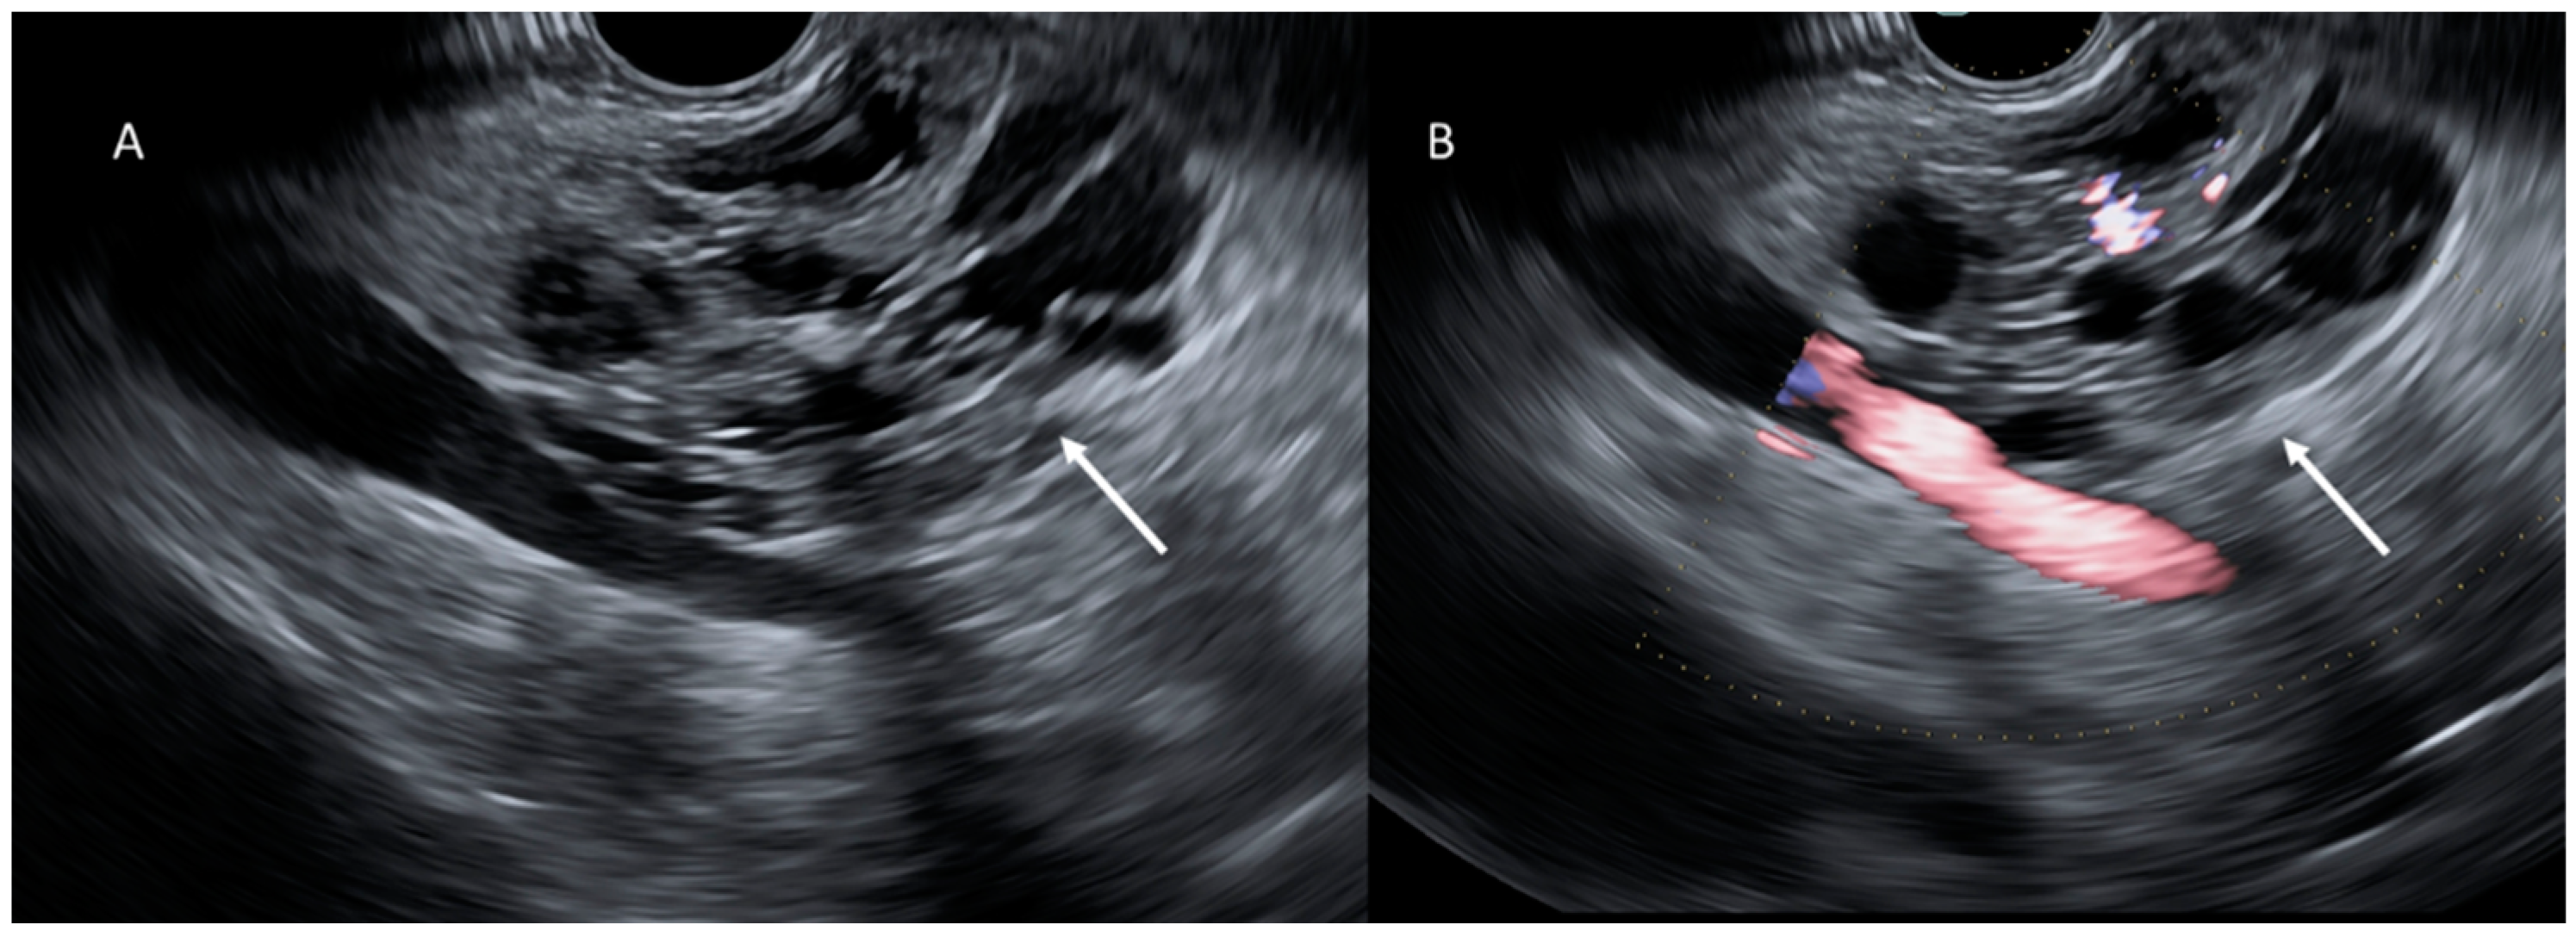

- Kitano, M.; Yoshida, T.; Itonaga, M.; Tamura, T.; Hatamaru, K.; Yamashita, Y. Impact of endoscopic ultrasonography on diagnosis of pancreatic cancer. J. Gastroenterol. 2018, 54, 19–32. [Google Scholar] [CrossRef] [PubMed]

- Jang, D.K.; Song, B.J.; Ryu, J.K.; Chung, K.H.; Lee, B.S.; Park, J.K.; Lee, S.H.; Kim, Y.T.; Lee, J.Y. Preoperative diagnosis of pancreatic cystic lesions: The accuracy of endoscopic ultrasound and cross-sectional imaging. Pancreas 2015, 44, 1329–1333. [Google Scholar] [CrossRef]